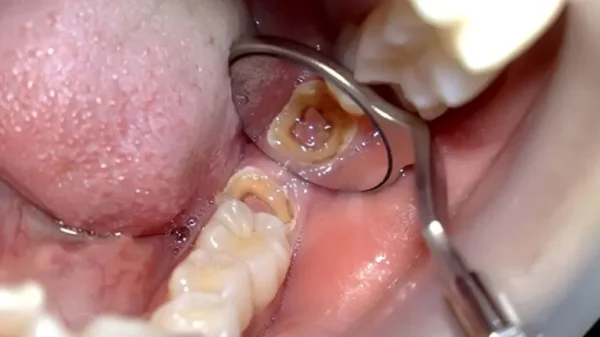

Bọc răng sứ hay còn gọi phủ răng sứ thẩm mỹ là một phương pháp giúp tạo thẩm mỹ và bảo vệ răng, tăng cường chức năng của các răng bị mẻ vỡ, sâu răng, mòn răng, mất răng, răng ố màu, đen xỉn…. Mang đến cho người dùng một hàm răng khỏe đẹp, trắng sáng tự nhiên khi cười, nói, ăn, nhai.

Tuy nhiên nếu bạn có một hàm răng thật xỉn màu, vỡ, mẻ, mất chất, răng đã lấy tủy, các trường hợp mòn răng nặng, răng nha chu lung lay, tái tạo khớp cắn chức năng, răng bị sâu phá hủy lớn, răng chấn thương, mất răng cần trồng mới… Những chiếc răng này làm bạn bị mất tự tin, đau buốt kéo dài, thậm chí tổn thương ngày một lan rộng và dẫn đến mất răng thì việc lựa chọn bọc sứ lại là giải pháp rất tốt. Răng sứ ra đời là một cuộc các mạng về phục hình răng trong nha khoa hiện đại.

Ưu điểm của bọc răng sứ hiện đại ngày nay là độ bền và độ lưu giữ cao do công nghệ ngày càng được cải tiến, vật liệu bọc răng sứ ngày càng tốt hơn, tạo ra những chiếc răng sứ chính xác vừa khít với răng thật và có màu sắc tự nhiên. Ngoài ra răng thật bị mài rất ít, không ảnh hưởng đến men răng và tủy răng như trước đây nữa. Răng sứ ngày nay còn có độ cứng chắc cao giúp lực nhai mạnh, cắn sắc bén.